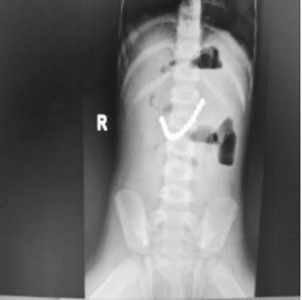

1.患儿:李某某,性别:男,年龄:2岁;简要病史:2岁男孩,因间断腹痛5天,发现消化道异物1天入院。5天前患儿无明显诱因出现腹痛,家长未予特殊重视,1天前患儿出现呕吐伴便秘,就诊于当地医院,行腹部X线片提示消化道异物(磁力球?),遂急诊就诊于我院,诊断“消化道异物(磁力球?)”收住我科。发病后患儿精神食欲差,予以开塞露后排大便1次,小便正常。既往身体健康,无家族遗传病史,心肺腹查体无异常。初步诊断:消化道异物(磁力球?)接下来,患儿需要做什么检查呢?是继续观察自行排出?还是内镜下取出?又或是剖腹探查取出呢?完善腹部X片 (两次间隔时间6小时)显示:磁力球位置未见明显变化(如下图),拟行手术治疗,手术方式为:剖腹探查术。手术探查示 (如下图):胃大弯处可见有2处直径约0.5cm穿孔 (穿孔内取出磁力球5颗),距屈氏韧带约40cm肠管近系膜侧可见2处直径约0.5cm穿孔 (穿孔内取出磁力球10颗),抗菌薇乔全层间断缝合一层胃大弯及小肠肠管穿孔,间断浆肌层加固一层;查无漏气漏液现象,吻合口直径通过顺畅。术毕。术后治疗:予以抗感染、肠外营养、过渡饮食对症治疗,患儿恢复顺利,康复出院。2.患儿:贾某某,性别:男,年龄:1岁10个月;简要病史:1岁10个月男孩,因精神反应欠佳伴烦躁哭闹4天入院。患儿于入院近4天精神反应欠佳,烦躁、哭闹,手捂腹部,呕吐2次,就诊于卫生所予以腹部外敷药物治疗,效果欠佳,后就诊于妇幼保健院,行腹部X片检查,提示消化道异物,自发病以来精神可,食欲欠佳,大便1次,小便量少。既往身体健康,无家族遗传病史,心肺腹查体无异常。初步诊断:消化道异物(磁力球?)完善腹部X片(两次间隔时间6小时)显示:磁力球位置未见明显变化(如下图),拟行手术治疗,手术方式为:剖腹探查术。手术探查示(如下图):距屈氏韧带约30cm小肠有2处直径约0.5cm穿孔(穿孔内取出磁力球1颗、螺丝1颗),距肛门口20cm处乙状结肠近系膜侧可见2处直径约0.5cm穿孔 (穿孔内取出磁力球9颗),据回盲部40cm处小肠系膜可见2处直径约0.5cm穿孔。术后治疗:予以抗感染、肠外营养、过渡饮食对症治疗,患儿恢复顺利,康复出院。